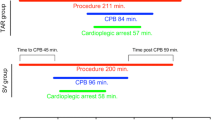

Operative data and technical outcome

L-BIMA + R-CABG was more often performed urgently and required longer operation times (Table 2), resulting in longer intubation time and longer ICU stay (Table 3). More distal anastomoses, especially on the RCA system, were performed in the L-T-BIMA + R-CABG group leading to improved completeness of revascularization (84% vs. 69%, p = 0.014). Higher total bypass flows and increased flow/anastomosis were also achieved with L-T-BIMA + R-CABG (Table 2).